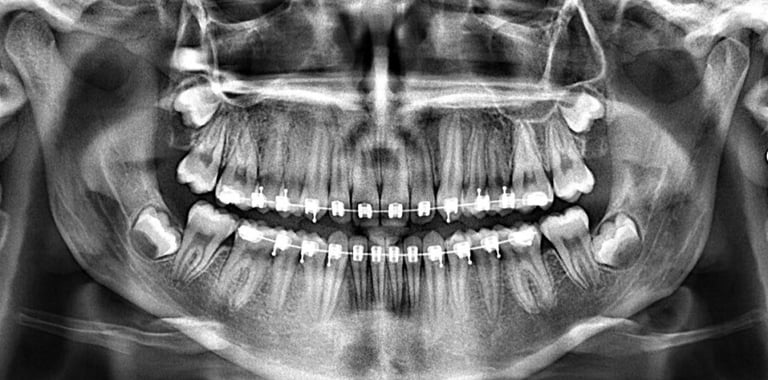

PANORÁMICA DIGITAL

Permite la evaluación de terceros molares, presencia de dientes retenidos, lesiones residuales y restos radiculares, permite ver anomalías del desarrollo, posición, desarrollo y forma de los dientes.

Además, permite ver traumatismos maxilofaciales, y lesiones óseas extensas.